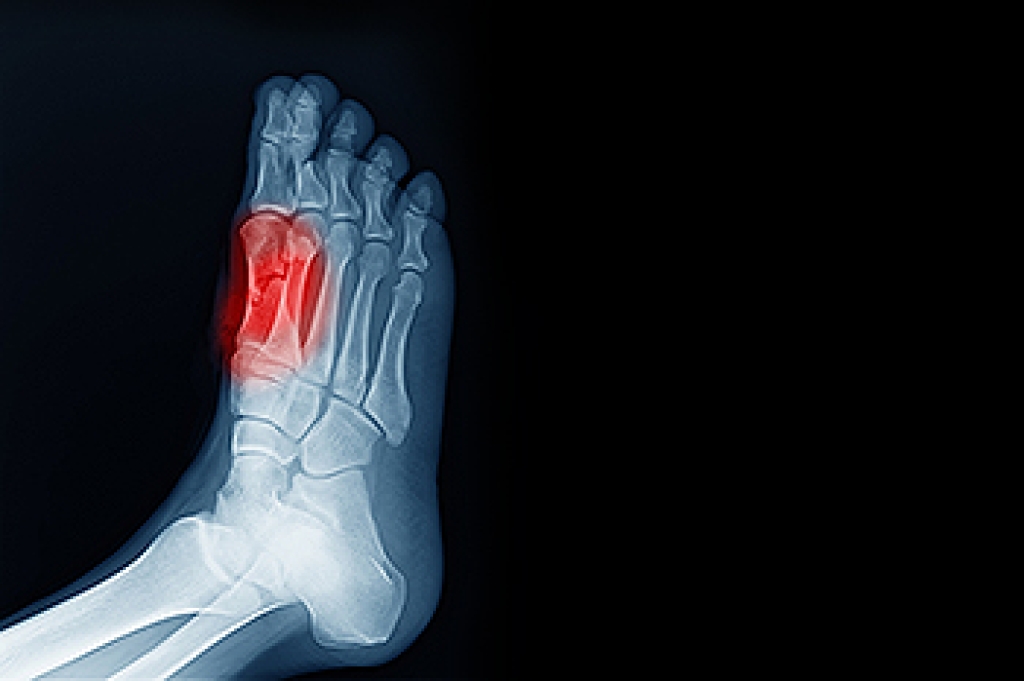

A broken toe occurs when one or more of the toe bones of the foot are broken after an injury. Injuries such as stubbing your toe or dropping a heavy object on it may cause a toe fracture.

Although the injured toe should be monitored daily, it is especially important to have a podiatrist look at your toe if you have severe symptoms. Some of these symptoms include worsening or new pain that is not relieved with medication, sores, redness, or open wounds near the toe.